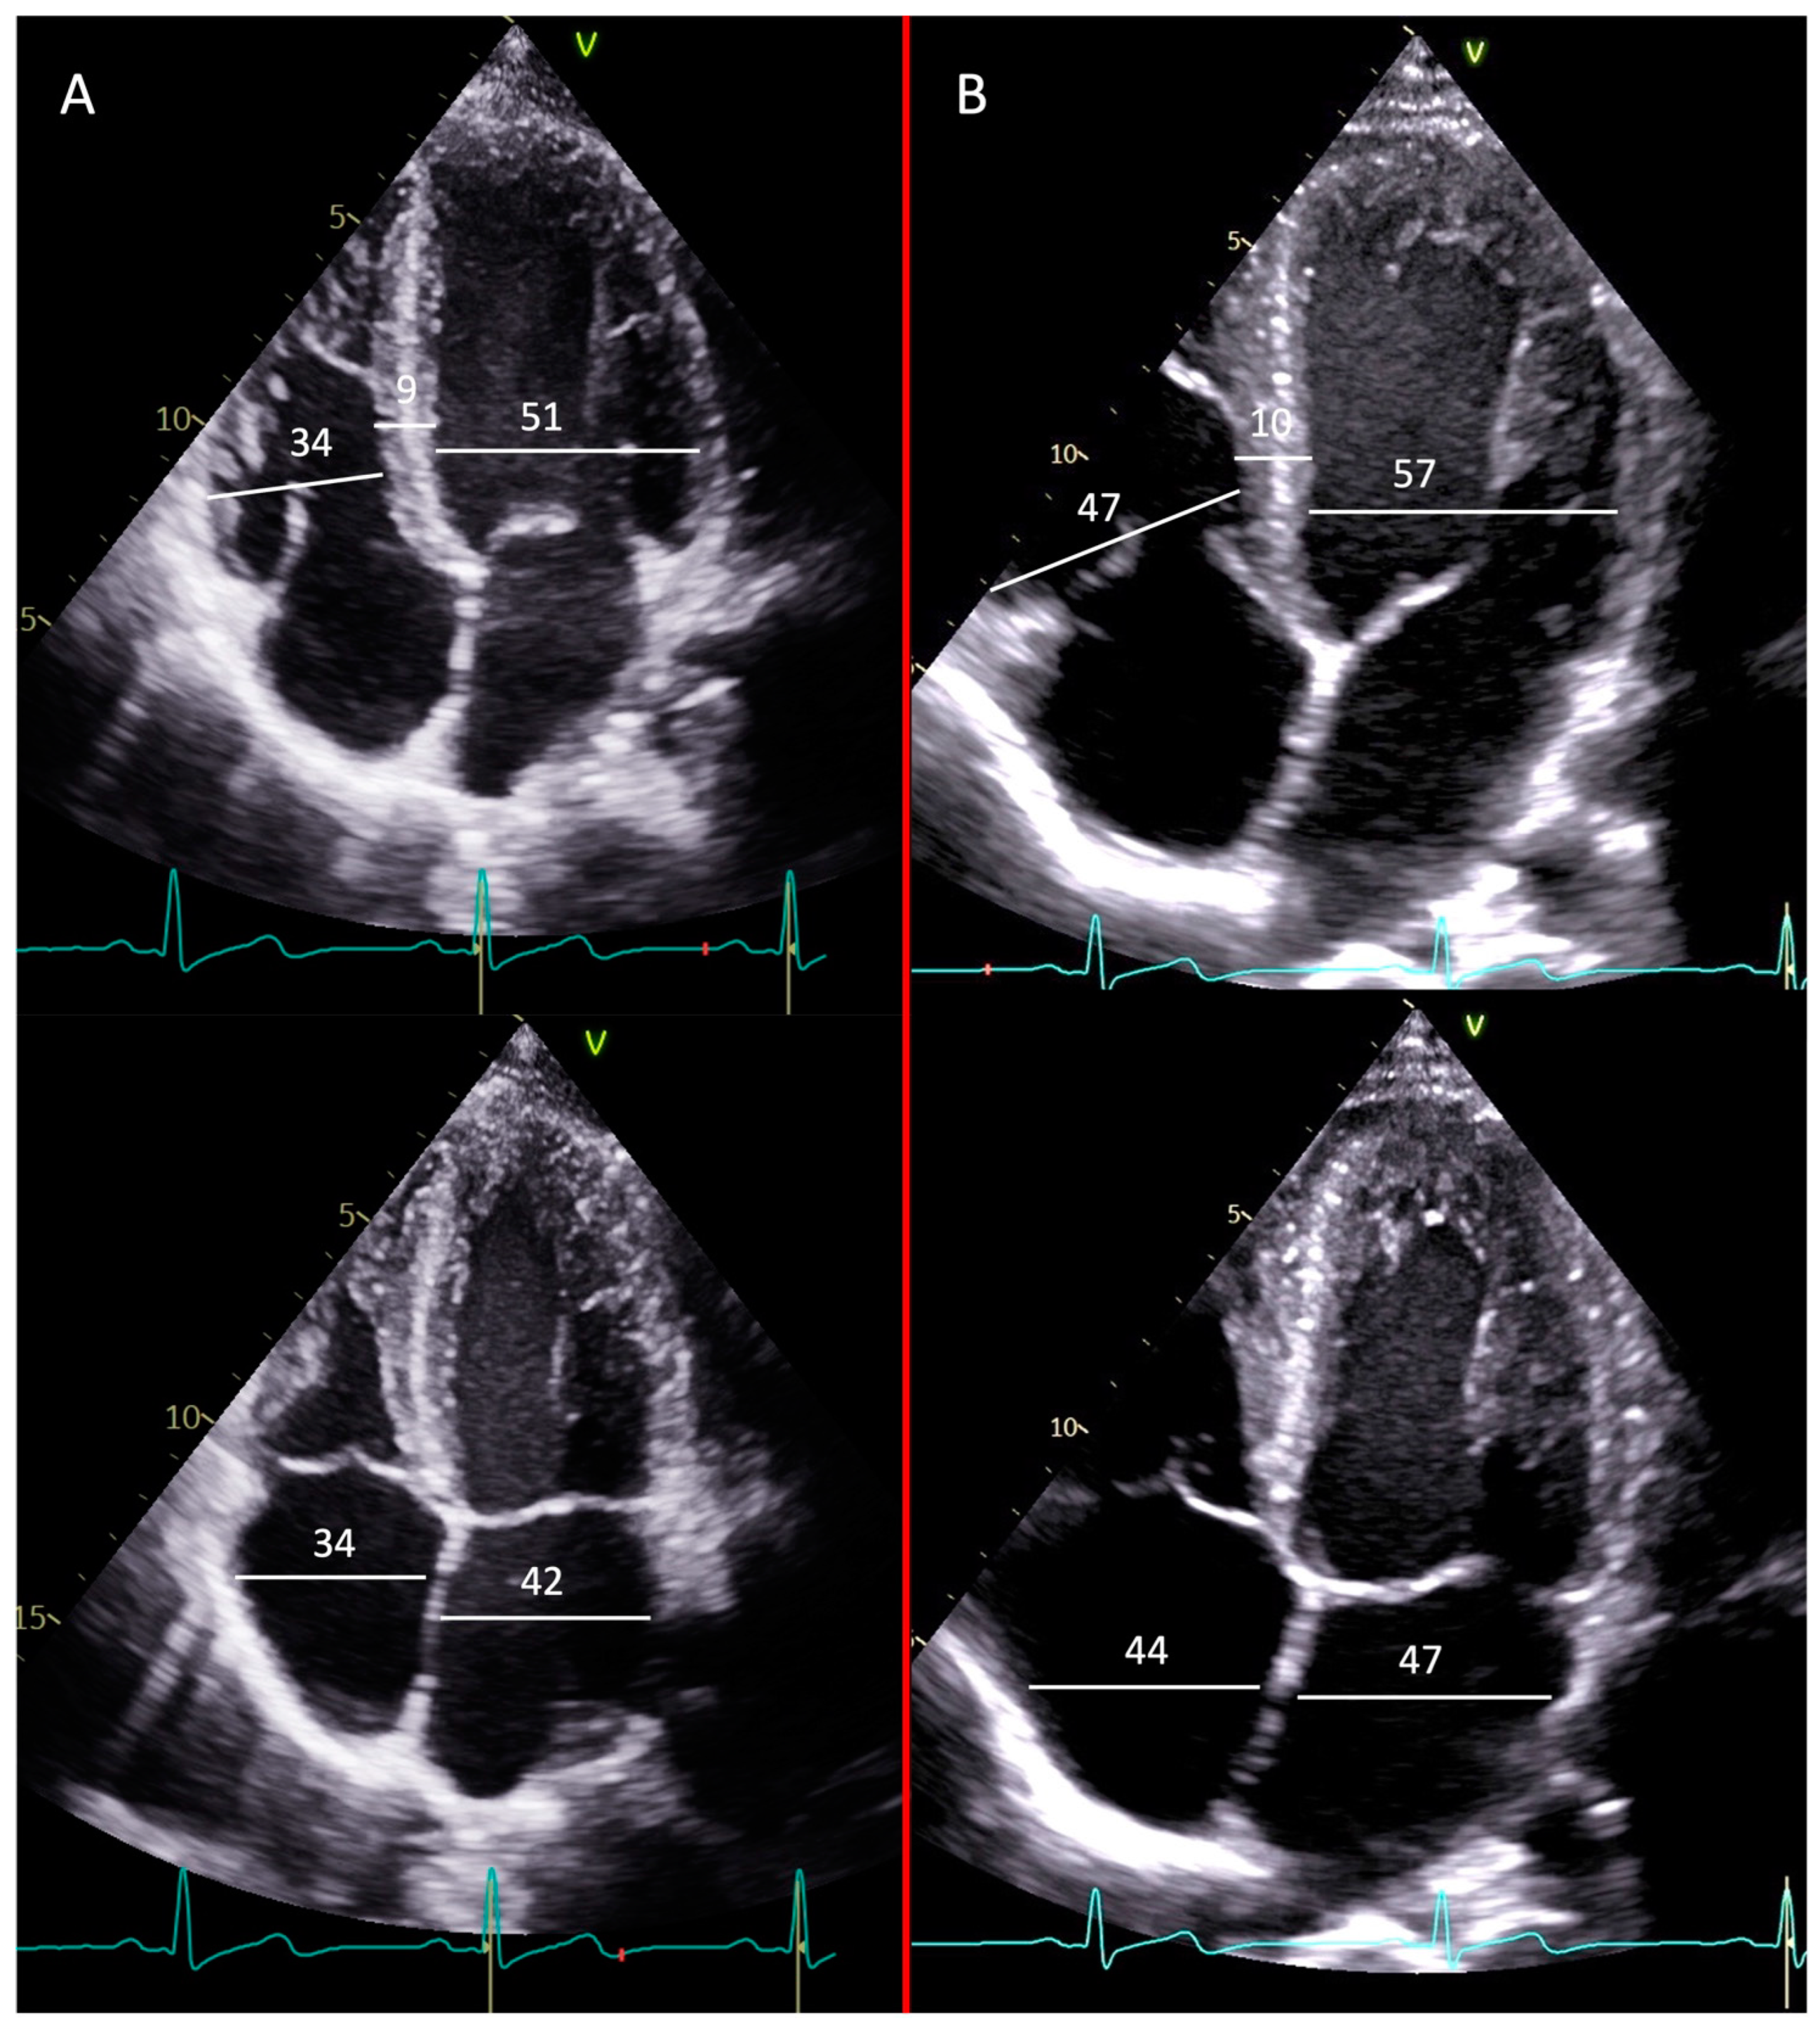

6. Results